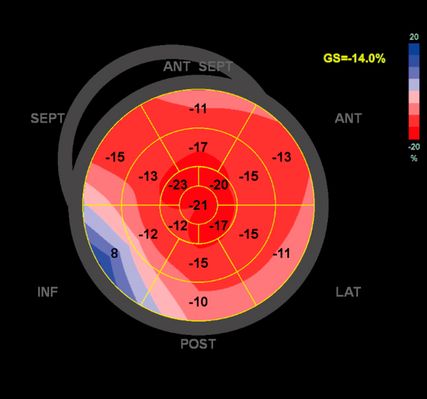

Dennoch ist die Echokardiografie aufgrund der niederschwelligen Verfügbarkeit als erste Untersuchungsmodalität und zur Verlaufsbeurteilung nicht wegzudenken. Mit der Ejektionsfraktion, der Vorhofgröße und der Beurteilung der diastolischen Funktion können prognostisch wichtige Parameter erhoben werden. Ein „apical sparing“ in der Analyse des myokardialen Strains oder der Aspekt eines „granular sparkling“ kann einen Verdacht auf kardiale Amyloidose begründen (Abb.3). Jede echokardiografische Untersuchung wegen des Verdachts auf LVH sollte außerdem eine Bestimmung des LVOT-Gradienten inkl. Valsalva-Manöver beinhalten (Abb.2).